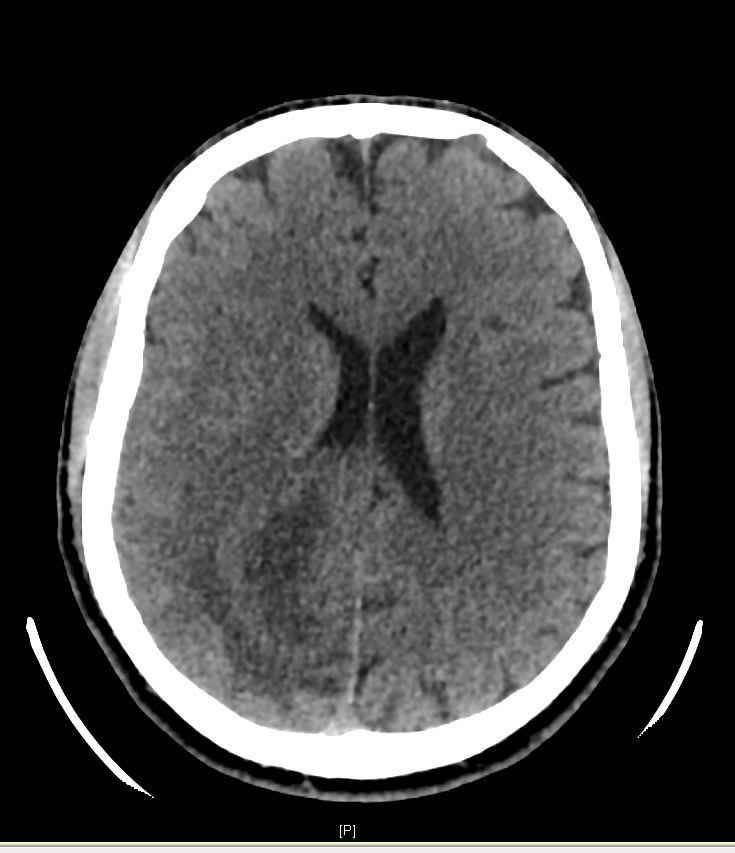

M. V., 41 ans, droitier, est adressé aux urgences où vous exercez, pour un épisode de mouvements cloniques hémicorporels gauches durant près de 10 minutes, sans perte de connaissance, avec un teint bleuté.

Son épouse ne rapporte pas d’antécédent particulier, il ne présente pas de troubles cognitifs. Elle signale tout de même que cela fait plusieurs fois qu’elle touche le bras gauche de son mari sans qu’il ne s’en aperçoive. De plus, il a récemment endommagé le rétroviseur côté conducteur de leur véhicule lors d’une manœuvre de stationnement. Il ne prend pas de traitement. Il ne fume pas et ne boit qu’occasionnellement. Il est sportif, en bon état général par ailleurs. Il se plaint parfois de céphalées avec sensation d’étaux, prédominantes à droite, qui résistaient aux antalgiques simples (paracétamol) depuis plus de 3 semaines.

Cliniquement, vous constatez une hémiparésie brachio-faciale gauche, apparue juste après l’épisode de mouvements anormaux et qui semble être en train de régresser selon les pompiers.